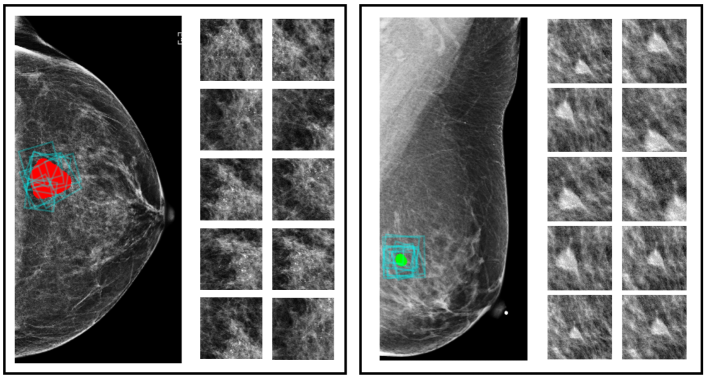

The first type of maps are saliency maps which represent global context. We generate the saliency maps by training a network on full-resolution mammography images to predict the presence of benign and malignant lesions in the breast. We refer to this network as the “context network.” We use Globally-Aware Multiple Instance Classifier [30, 17] as the context network, which is explicitly designed to provide interpretability by highlighting the most informative regions of the input images. To be more precise, the feature maps obtained after the last residual block of the context network are transformed by a convolutional layer with sigmoid activation into two saliency maps, denoted as and . Each pixel in the saliency map corresponds to a region in the full image, and its element denotes a score indicating the contribution of this region towards classifying the input image as containing malignant lesions or benign tissues. A pair of saliency maps for an image is shown in Figure 2.

In this study, we consider lesion-level classification, and design models to directly distinguish biopsy-confirmed lesions as being either benign or malignant. With this strategy, we enable the models to make accurate lesion-wise predictions. To show that deep learning approaches can benefit from utilizing global image context in classifying local findings on mammograms, we first train DNNs with cropped image patches to enable the learning of fine details from a specific region, then integrate the extracted local information with the global context. The global context is provided in the form of saliency maps (Figure 2) extracted by a model classifying the entire image. Here we use Globally-Aware Multiple Instance Classifier [17] as the model to provide such saliency maps. In addition, we evaluate the models’ performance on a challenging population which consists only of cases that are difficult to diagnose and the radiologist requested a biopsy for. This further differentiates our work from previous works [16, 30, 17, 13, 18] and makes our results not directly comparable to theirs. This is because these methods were developed and evaluated for the screening population, which contains a lot of negative cases not requiring biopsy, which can inflate their evaluation metrics [16].